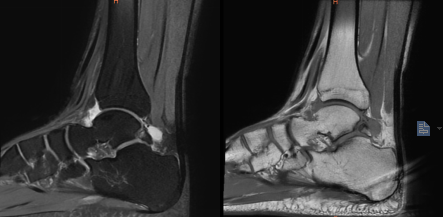

術前MRI顯示左踝副骨綜合征

一位19歲大學生,由于左踝長期疼痛,輾轉多家醫院癥狀未緩解,嚴重影響其學習生活,經人介紹來到我院骨科治療。骨科副主任(主持工作)彭李華博士為其進行了全面專業的檢查,發現為三角籽骨綜合癥。完善術前檢查及準備后,彭李華博士為患者行“踝關節全內鏡下清理、松解術”。患者對手術效果滿意,已順利出院。